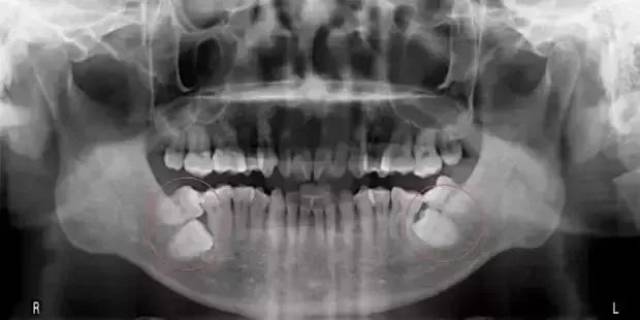

健康牙齿拍片图

健康牙齿拍片图,正常牙齿健康牙齿图片

正常牙齿健康牙齿图片

牙齿拍片图片

正常牙齿拍片图片

标准牙齿拍片图

牙齿拍片解析图

健康牙齿x光片

牙齿拍片解析图正常

正常牙齿拍片